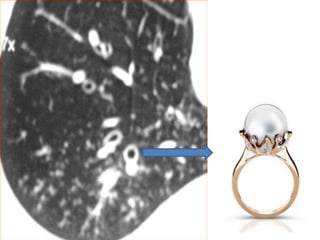

 Signet ring appearance on CT: normally, the

vessel is larger than the corresponding

bronchus; in bronchiectasis, the bronchus is

larger than the corresponding vessel.

 Bronchial dilation, the cardinal sign of

bronchiectasis, is characterised on HRCT by a

bronchoarterial ratio (BAR) of .1, lack of

bronchial tapering, and visibility of airways

within 1 cm of the pleural surface or abutting

the mediastinal pleural surface.